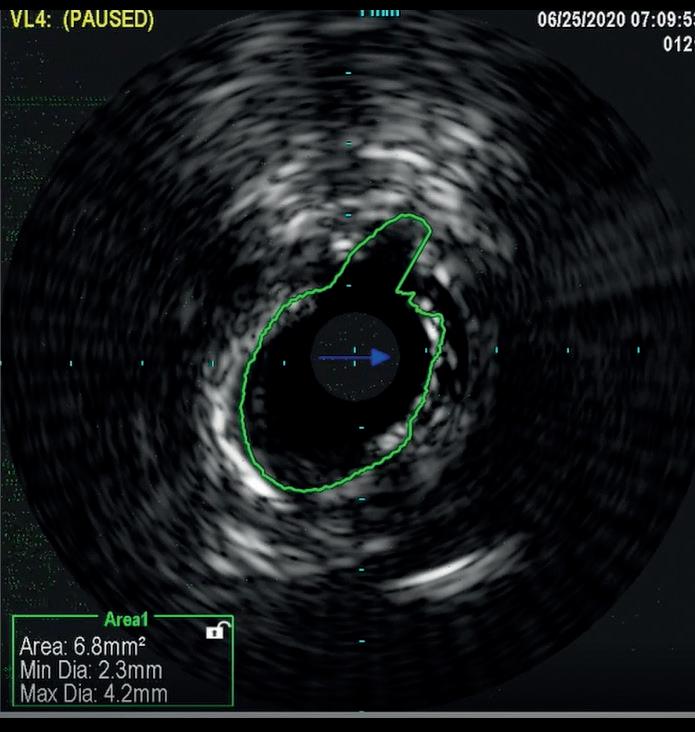

In a similar fashion, IVUS was used to evaluate elastic recoil following the use of IVL in a 61-year-old female patient with a history of diabetes, hypertension, high cholesterol, chronic kidney disease, and coronary artery disease. She presented with left lower extremity rest pain. Her baseline angiography showed two target areas with calcified stenotic disease that were treated (distal SFA and TPT). As shown in Figure 2, there was only an 8.8% loss of luminal gain in the max calcium portion of the TPT vessel 15 minutes after IVL treatment. Based on early and limited evaluations, IVL shows promising results with excellent luminal gain and with minimal luminal compromise, as evidenced on IVUS. Anecdotal cases have been encouraging and further studies are warranted to better understand if this mechanism of action provides the ability to ultimately produce significant luminal gain with minimal acute recoil. If this hypothesis holds true, this technology may lead to

Figure 2a. IVUS image of the most calcified aspect of TCT lesion immediately post-IVL